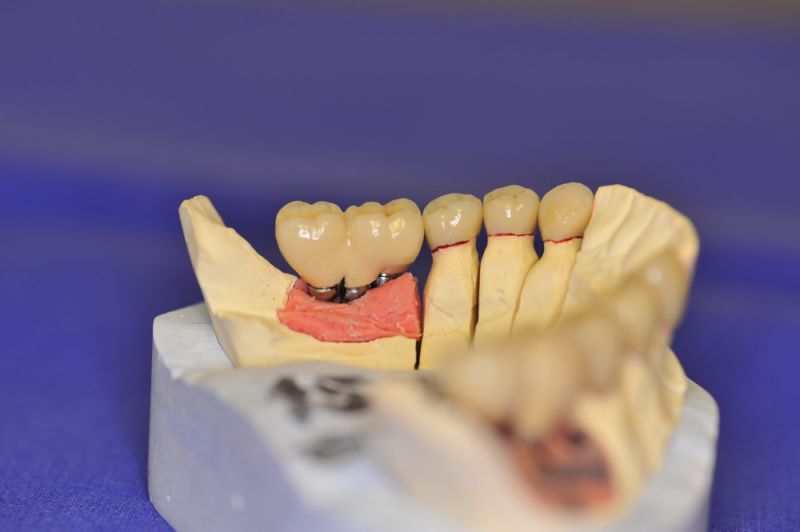

Eine der technisch anspruchsvollsen Arbeiten, die hier je erstellt worden ist

Mit dem heutigen Tag geht eine der technisch schwierigsten und anspruchsvollsten Arbeiten zu Ende, die im CMD-CENTRUM-KIEL jemals erstellt worden ist. Dabei sind es nur 10 Kronen, die benötigt werden, um die starken Kopf- und Gesichtsschmerzen der Patienten zu beseitigen.

1. Notwendigkeit einer implantatgestützten Kronenversorgung mit der Vorgeschichte, dass die Patientin eine Vielzahl von Behandlern aufgesucht hatte, die eine Implantation im Unterkiefer als nicht durchführbar einschätzten.

2. Extrem schlechte knöcherne Verhältnisse im Unterkieferseitenzahnbereich, die sich intraoperativ noch einmal als ungünstiger darstellten, als bereits in den Voruntersuchungen erkennbar.

3. Sehr dünne Implantate, die von ursprünglich zwei je Kieferhälfte auf letztendlich drei je Kieferhälfte umgeplant werden mussten.